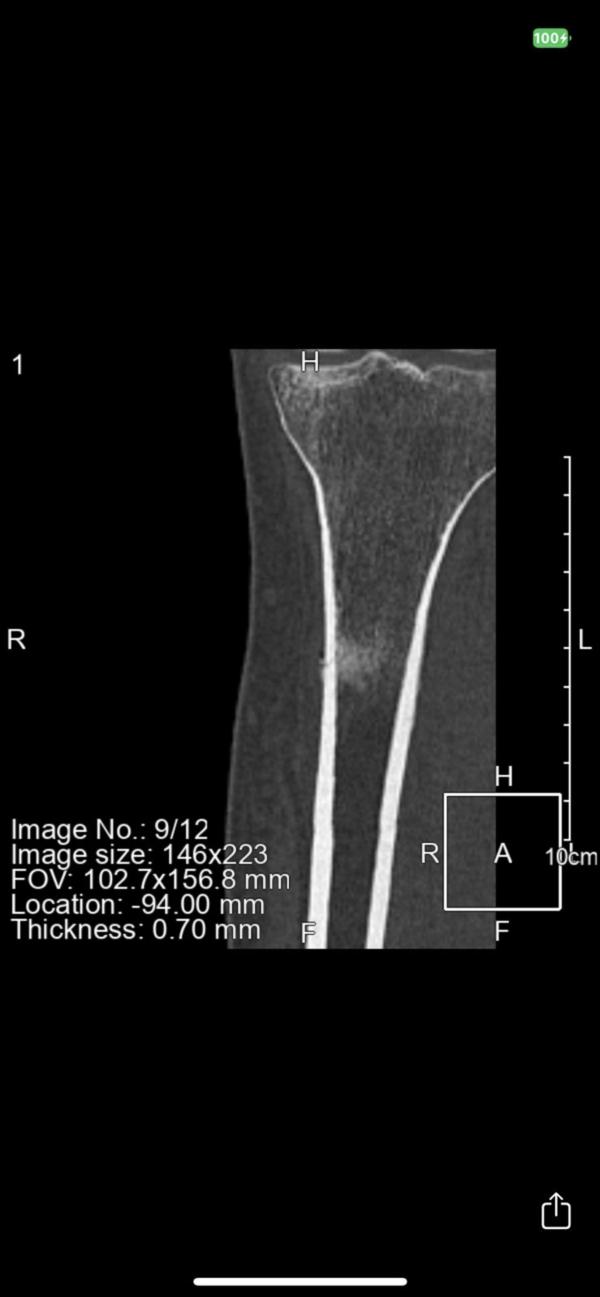

1 октября была спортивная травма , поставили стресс-перелом,лечила . Далее делала МРТ,КТ после которых направили к онкологу . 2 врача сказали что мол все нормально,вы зря паникуете и без назначения анализов опровергающих описание МРТ отправили домой. Я ,в надежде что все хорошо,продолжаю лечение стресс-перелома и сегодня делаю контрольное МРТ , на котором видны не улучшения ,а ухудшения😭

1 фото это МРТ в начале,2 которое сделала вчера. За 2 месяца это все расползлось и снова отправляют к онкологу😔

Костная ткань так же изменена и + изменен картикальный слой (раньше этого не было)